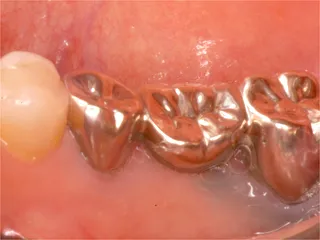

| 自費治療 インプラント |

治療前

インプラントは第二の歯とも呼ばれ 顎の骨に金属製のネジを立てて 人工の歯を取付けます 当院では高い技術と経験で対応しています ■長所 ・しっかり噛むことができる ■短所 ・禁忌症がある ・高い インプラント・くわしく |